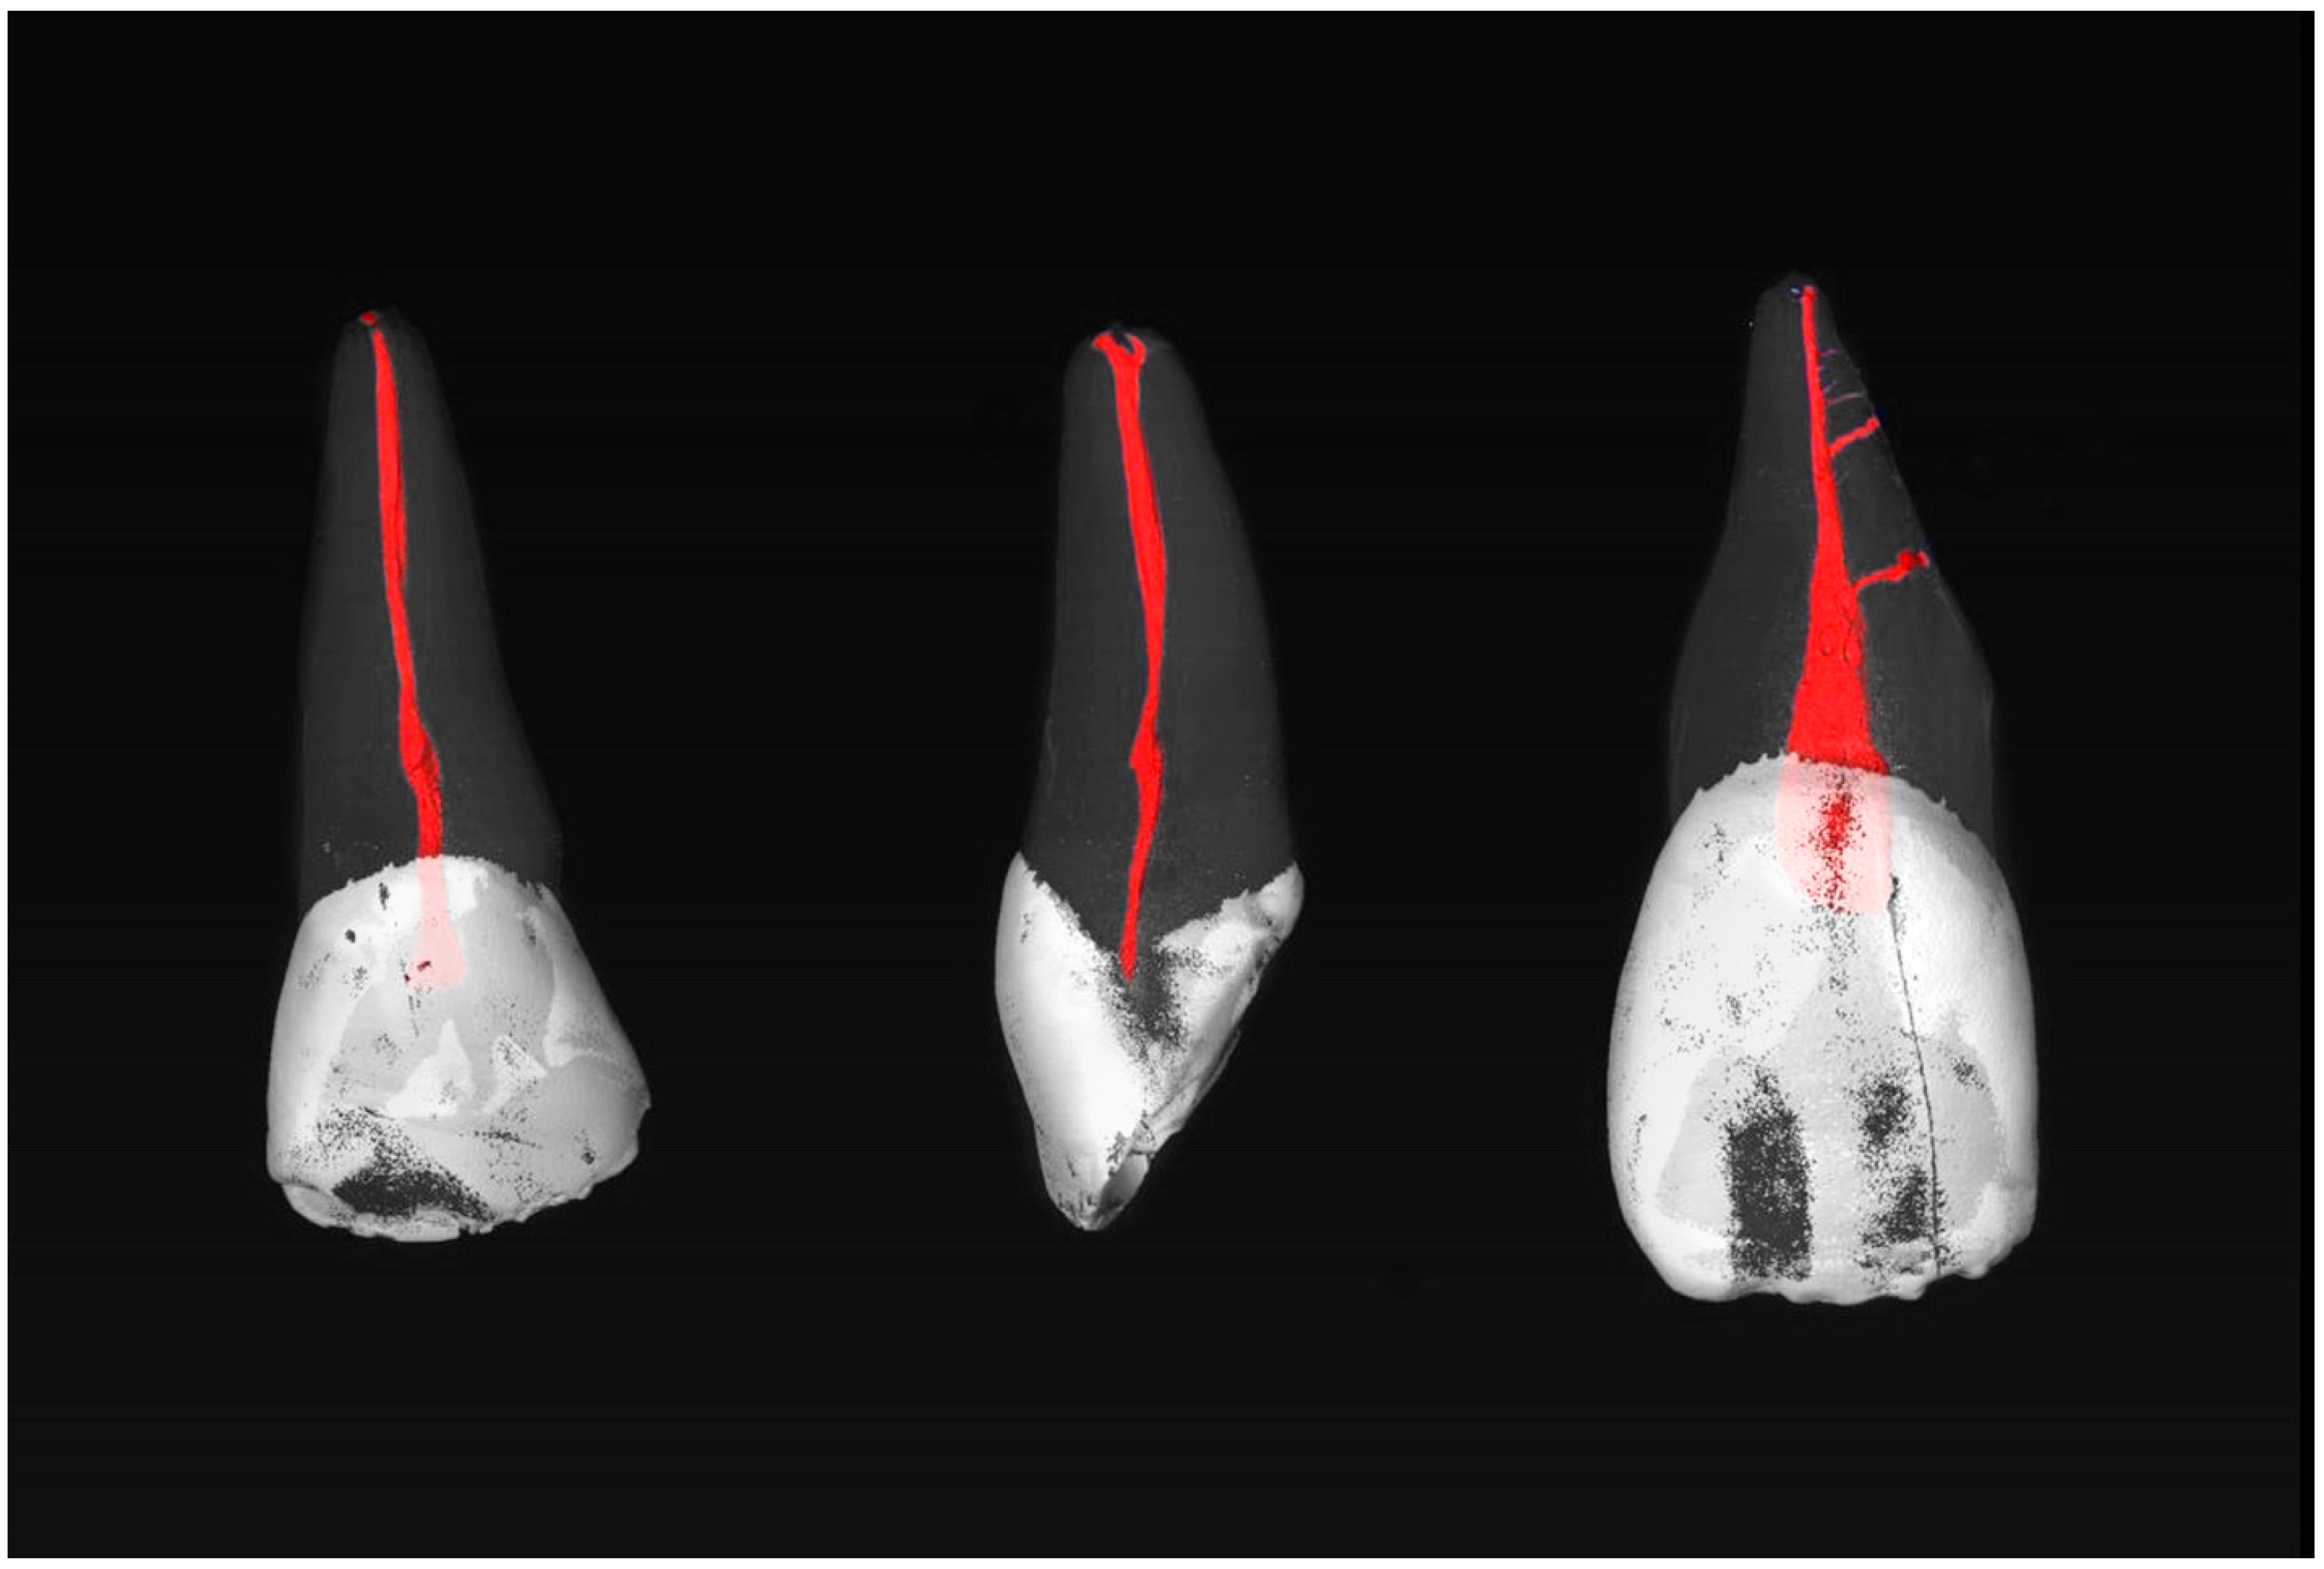

Most commonly, the MxCIs had no accessory apical foramina (85.7%). One (8.0%), two (3.6%), three (0.9%), or four (1.8%) could be observed (diameter > 0.1 mm). Examples of the MxCI specimens are shown in Figure 1 and Figure 2.

Figure 1.

µCT images of maxillary central incisors with a 1-1-1/1 RCC (left) and 1-1-1/2 RCC (center) without accessory canals, and a 1-1-1/1 RCC (right) with two accessory canals in the middle root third.